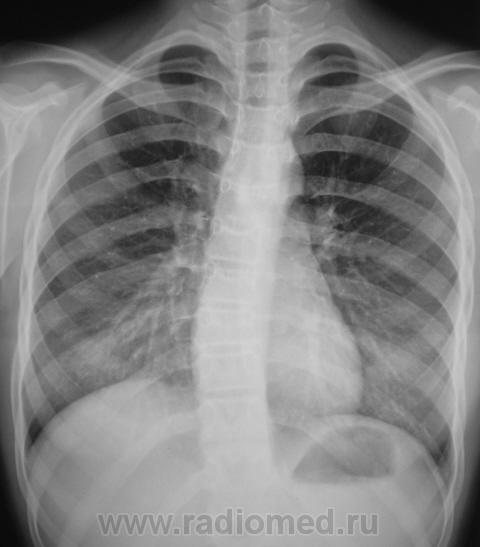

Пациент направлен на рентгенографию ОГК по поводу виража.

Как трактовать изменения в грудном отделе позвоночника, как сколиоз или как сколиотическую осанку?

Валентин Львович, здравствуйте.Боковая клиновидность тел позвонков на уровне искривления присутствует, что говорит в пользу сколиоза-так нас учили.Ротация тоже имеется.

Хотелось бы попросить опытных рентгенологов, которым часто приходится сталкиваться с ВВК, показать на данных снимках торсию и ротацию.

... и, чтобы было удобнее - снимки с увеличением.

[[wysiwyg_imageupload:257:]][[wysiwyg_imageupload:258:]][[wysiwyg_imageupload:259:]][[wysiwyg_imageupload:260:]]

Насколько я понимаю, рентгенологически торсия проявляется на фронтальном снимке смещением корней остистых отростков на высоте искривления в ВОГНУТУЮ сторону. Смещение корней ДУЖЕК говорит о ротации. Или я не прав?

"Отклонение линии остистых отростков во фронтальной плоскости, сопровождающееся легкой асимметрией надплечий, углов лопаток, треугольников,талии и позиции таза. Асимметрия исчезает при горизонтальном положении и при наклоне вперед. Сколиотическая осанка не сопровождается ротацией и торсией позвонков."-цитата из " Вертебрологии"Э.В.Ульриха,А.Ю.Мушкина.Думаю, что боковая клиновидная деформация может быть как врожденной так и приобретенной.

Хм, судя по вышеоптсанному - в вышеуказанном случае максимум можно поставить 1-ю степень торсии. (корни дуг распологаются симметр чно относительно остистых отростков и боковых сторон тела, ну, может есть небольшая ассиметрия самих корней Или я чего то не так понял, или плохо смотрю :(